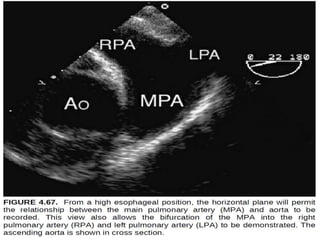

By

withdrawing the probe slightly and adjusting to a more

horizontal plane

(approximately 0 degrees), the bifurcation of the main

pulmonary artery can

be visualized adjacent to the ascending aorta

By withdrawing the probeslightly and adjusting to a more horizontal plane (approximately 0 degrees), the bifurcation of the main pulmonary artery can be visualized adjacent to the ascending aorta